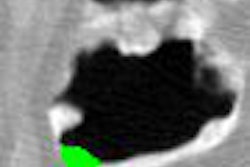

| In the intensity-based CAD scheme, the local intensity structure on the CT images is approximated by fitting the surface to the neighborhood of each voxel. The Hessian matrix is then calculated using the partial second derivatives of the fit surface. The eigenvalues of the Hessian matrix correspond to the maximum and minimum values of the second derivatives. Eigenvalue profiles are distinct depending on whether the structures are in air/lumen regions (above) or tagged fecal material (below), generating distinct output on the blob enhancement filter inv-blob enhancement filters used to cull false-positive detections. The output of these two filters is applied to the CT images. |

![]() |